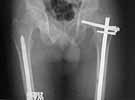

We managed to get neutral phosphate, initiated medical treatment and did an antegrade SIGN nailing of left femur along with couple of screws to neck using miss a nail technique. He complained of pain of the right femur and both forearms. In OT these areas were screened using image intensifier and found that he has looser zones of all these with impending fractures. Yesterday we did a retrograde nailing of right femur usingSIGN nail. Both ulnas were stabilised usingLambrudini wires in a closed fashion. All fractures and looser zones were stabilised by closed surgery using image intensifier. It may be interesting to see the post of picture of both the hips in which one side shows an antegrade femoral SIGN nail and the other side shows a retrograde SIGN nail.